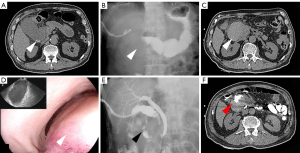

Five days after discharge, the patient revisited the emergency department with bleeding from the drainage tube in the descending duodenum. Another CT scan was performed to make a diagnosis (Figure 3).

The plain CT revealed another confined, hyperdense mass at the third part of duodenum, and the diagnosis was recurrent IDH.